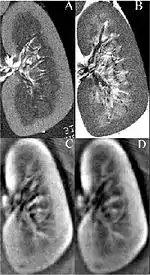

Fig. 1. Bottom: The first 3D thermoaoustic images of biologic tissue (lamb kidney). Top: MRIs of the same kidney.

Thermoacoustic imaging was originally proposed by Theodore Bowen in 1981 as a strategy for studying the absorption properties of human tissue using virtually any kind of electromagnetic radiation.[1] But Alexander Graham Bell first reported the physical principle upon which thermoacoustic imaging is based a century earlier.[2] He observed that audible sound could be created by illuminating an intermittent beam of sunlight onto a rubber sheet. Shortly after Bowen's work was published, other researchers proposed methodology for thermoacoustic imaging using microwaves.[3] In 1994 researchers used an infrared laser to produce the first thermoacoustic images of near-infrared optical absorption in a tissue-mimicking phantom, albeit in two dimensions (2D).[4] In 1995 other researchers formulated a general reconstruction algorithm by which 2D thermoacoustic images could be computed from their "projections," i.e. thermoacoustic computed tomography (TCT).[5] By 1998 researchers at Indiana University Medical Center[6] extended TCT to 3D and employed pulsed microwaves to produce the first fully three-dimensional (3D) thermoacoustic images of biologic tissue [an excised lamb kidney (Fig. 1)].[7] The following year they created the first fully 3D thermoacoustic images of cancer in the human breast, again using pulsed microwaves (Fig. 2).[8] Since that time, thermoacoustic imaging has gained widespread popularity in research institutions worldwide.[9][10][11][12][13][14][15] As of 2008, three companies were developing commercial thermoacoustic imaging systems – Seno Medical,[16] Endra, Inc.[17] and OptoSonics, Inc.[18]